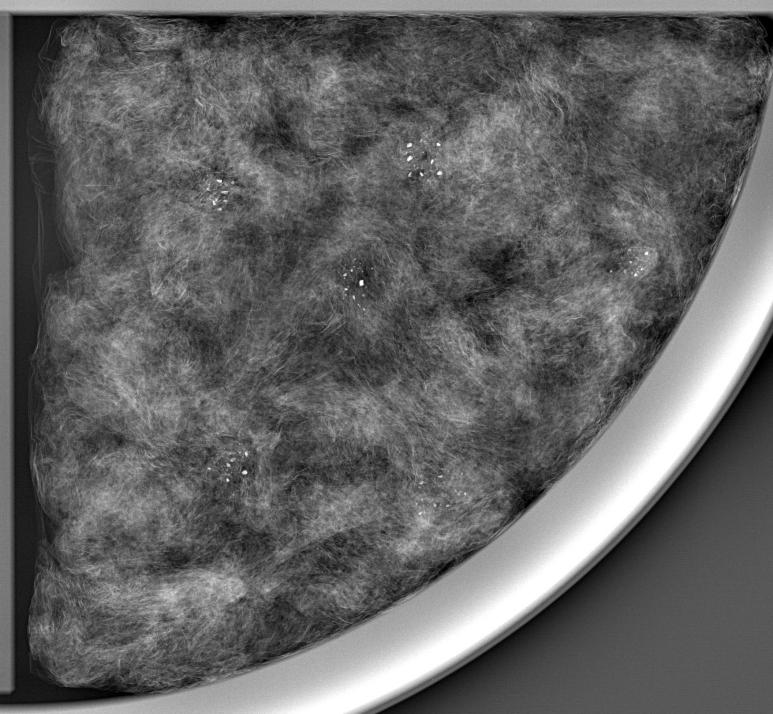

Merak1215A探测器下的乳腺成像

初期的乳腺癌往往没有明显的症状,因此专门的检查如核磁共振或乳腺活检并不会作为常规首选。相比之下,X射线摄影和超声检查由于其操作简便、技术成熟且成本相对较低的优势,被广泛采用并成为许多国家和地区推荐的标准筛查方法。其中X射线摄影利用低剂量的X射线捕捉乳房深层图像,能快速识别出肿块或钙化等潜在异常。

作为国内首家掌握晶圆级CMOS图像传感器芯片设计能力及CMOS平板探测器量产工艺的国家高新技术企业,善思微致力于以更加先进和安全的技术赋能医疗健康,让每一次的乳腺筛查都变得更加准确、更加安全,也更加普惠。我们的探测器不仅是技术上的突破,更是对生命的深切关怀,是对全球女性健康的一份深情守护。